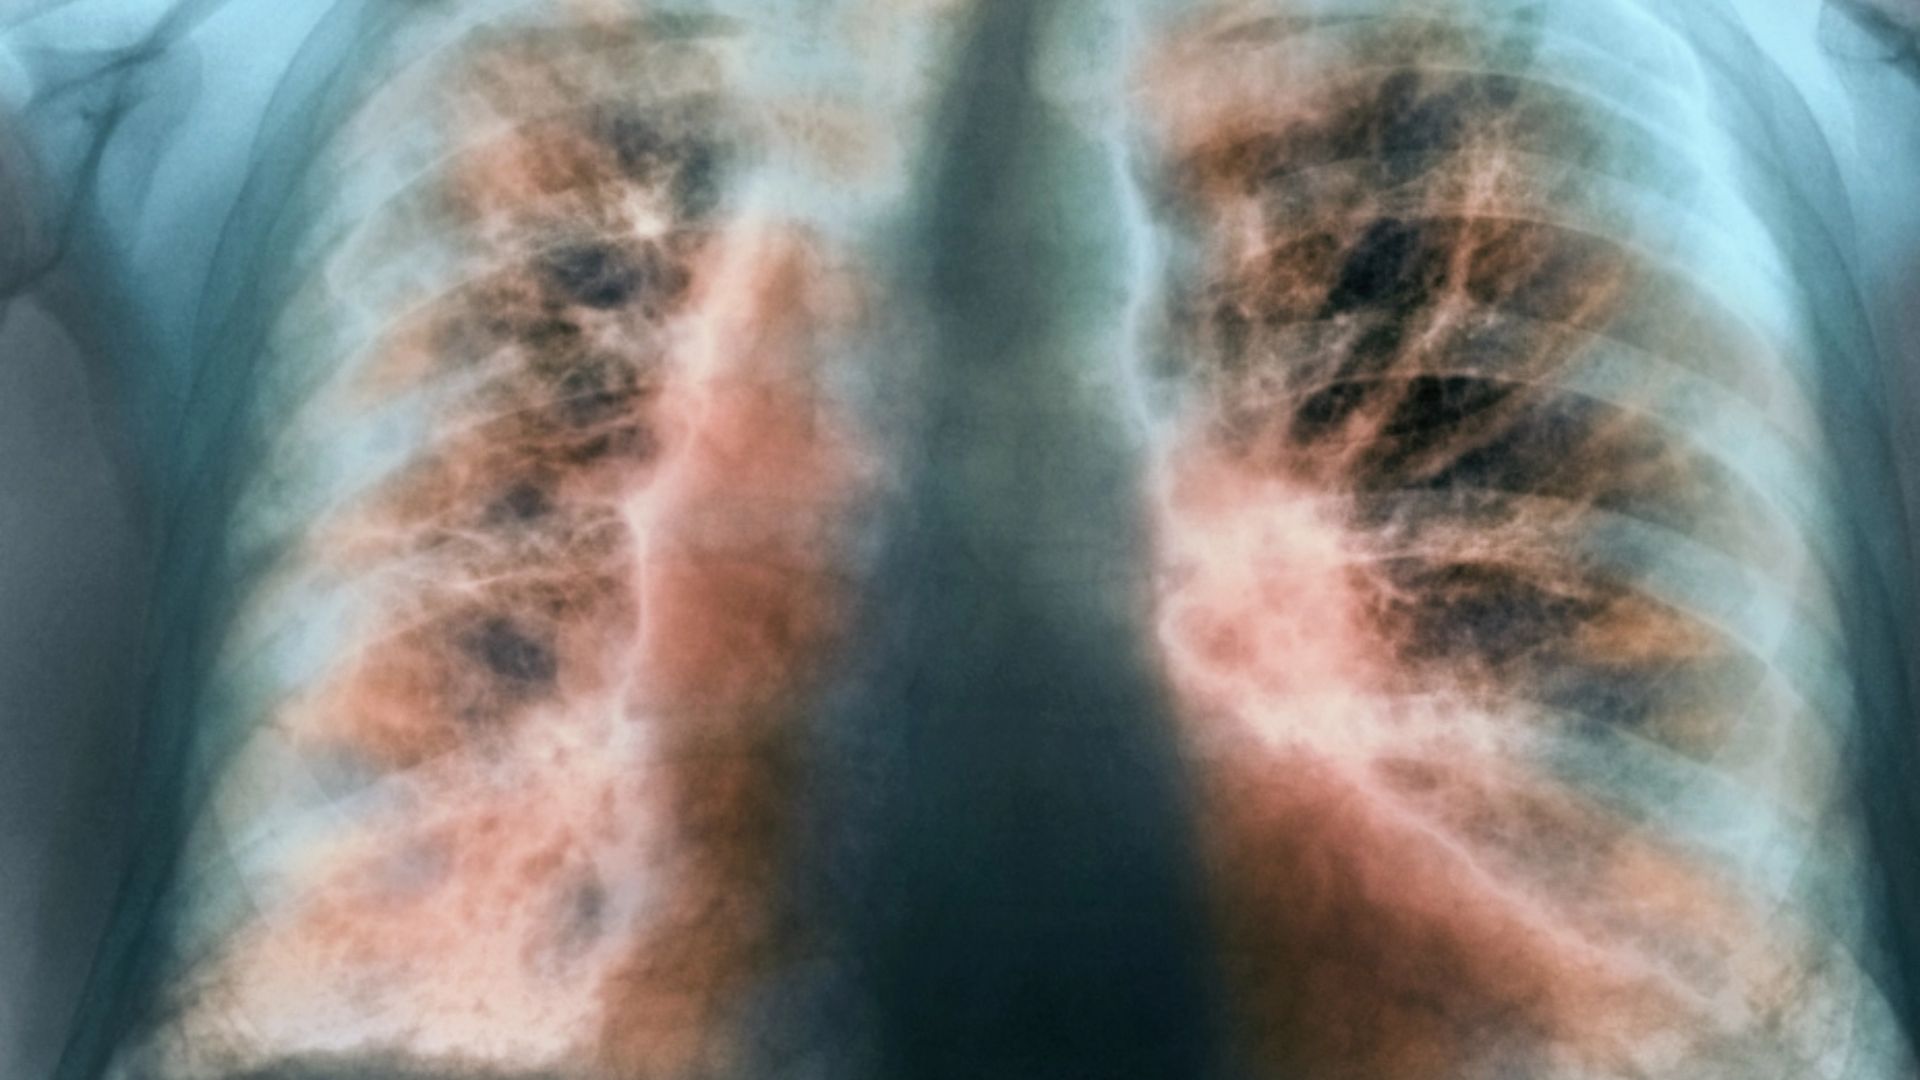

ডা. আব্দুস শাকুর খান বলেন, ফুসফুসের ক্যানসার হচ্ছে ফুসফুসের এক ধরনের টিউমার। অর্থাৎ ফুসফুসের যে স্বাভাবিক কোষ আছে সেই স্বাভাবিক কোষের যখন অস্বাভাবিক এবং অনিয়ন্ত্রিত বৃদ্ধি হয়ে চাকার মত সৃষ্টি করে, তাকেই ফুসফুস ক্যানসার বলে। এটি শরীরের জন্য মারাত্মক ক্ষতিকর। ক্যানসার যখন ফুসফুসে হয় এটা শুধু নির্দিষ্ট জায়গায় থাকে না বরং অস্বাভাবিক এবং অনিয়ন্ত্রিত বৃদ্ধির কারণে শরীরের অন্যান্য অংশেও ছড়িয়ে পড়ে। সঠিক সময়ে শনাক্ত ও যথাযথ চিকিৎসার অভাবে শেষ পর্যন্ত মৃত্যুরও কারণ হয়ে থাকে।

ফুসফুস ক্যানসারের অন্যতম লক্ষন হচ্ছে দীর্ঘমেয়াদী কাশি হওয়া, কখনো কখনো কাশির সঙ্গে কফ এবং কফের সঙ্গে রক্ত যাওয়া। ফুসফুসের ক্যানসারের কারণে বুকে ব্যথা হতে পারে। ক্যানসার যদি ব্যাপকতা পায় এবং বুকে পানি চলে আসে অথবা ফুসফুসে বেশি ছড়িয়ে পড়লে শ্বাসকষ্ট হতে পারে। এছাড়া কিছু সাধারণ লক্ষণ আছে, যেগুলো সব ক্যানসারেই দেখা যায়। যেমন- ওজন কমে যাওয়া, খাবারে অরুচি।